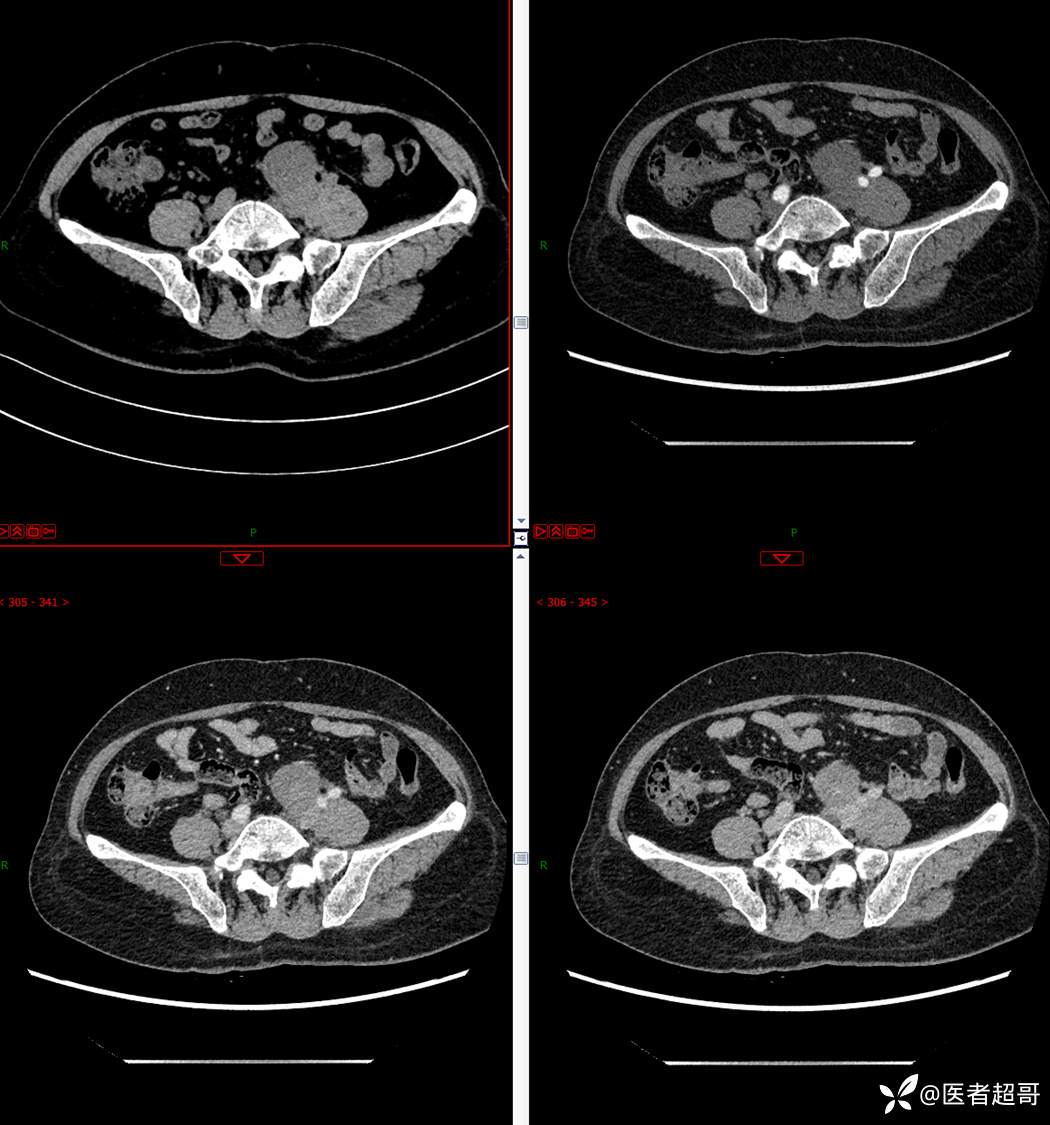

【影诊笔记559】查体发现右输尿管结石1周,发现腹膜后肿物,请分析,有病理!

•主 诉:查体发现右输尿管结石1周。

•现病史:患者1周前因小便不适来我院门诊行彩超检查提示右输尿管结石并右肾积水,伴腰疼,无血尿,无寒战,高热,患者求其进一步诊治,门诊以“右输尿管结石并右肾积水”收入院,患者自发病以来,神志清,精神可,饮食睡眠可,大便便秘,近期体重无明显增减。